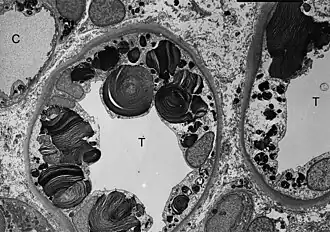

ТЭМ-микроскопия показывает наличие включений гликосфинголипидов различной формы и размеров в клетках дистальных канальцев почки. | |